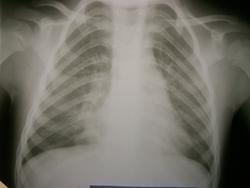

До этого с 21.05 по 28.05 лежал в детском отделении и по снимкам я ставила нижнедолевую пневмонию справа.

Самостоятельно родители свозили реьенка в область. Рентгенолог областной детской больницы описала, что инфильтрации нет, а есть сгущение легочного рисунка в нижней доле справа. И в заключении выставила " признаки обструктивного синдрома".

Первые 2 снимка сегодня, вторые 2 майские.